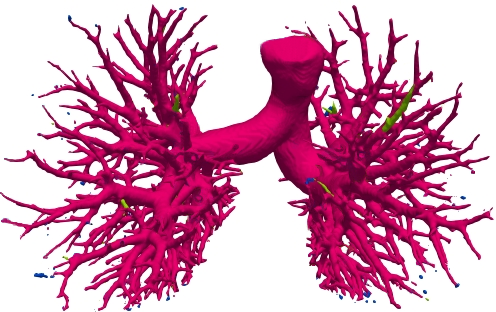

We qualitatively analyze our method on four challenging lung organ datasets. In Fig. 5, SFCN [19] suffers from severe false positives and some false negatives, especially for the big green areas of airway leakages. WNet [22] is mainly influenced by false negatives on the main trachea. For the Fibrosis dataset at the third row, it also encounters the false negative problem in the terminal bronchioles moderately. FANN [10] bears the slight discontinuity issue of false negative in the terminal bronchioles of BAS dataset, and the severe discontinuity and airway leakage problems on the more challenging Fibrosis benchmark. Instead, due to the above two novel modules, our method can solve the defects of false negative, discontinuity, and leakages faced by past advanced methods. Besides, the results on PARSE22 artery dataset in supplementary Fig. 6 also proves this.

Comparison on PARSE22 dataset. This dataset is more challenging due to more dense small bronchioles shown in supplementary Fig. 6. However, our method still reaches the best weighted average multi-level dice of 84.96% in Table 2 compared against some advanced methods via the official evaluation. As you can see, the remarkable gain comes from the “branch artery”, which maintains the consistency with above airway segmentation.